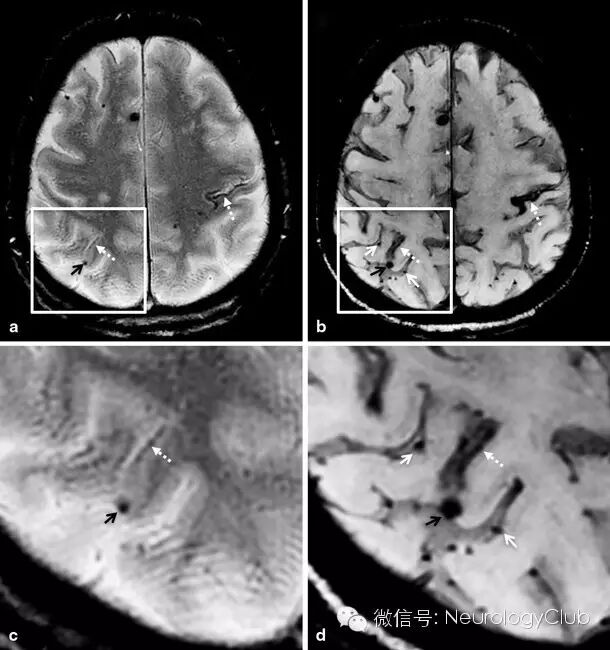

(73岁脑淀粉样血管病患者可见多发微出血和局部表面铁沉积。脑微出血[a-d黑箭和c-d白箭]和局部表面铁沉积[a-d虚白箭]在SWI[b,d]上较T2*WI[a,c]表现出更明显的低信号和更大的直径。c-d分别为a-b中框出部位的放大